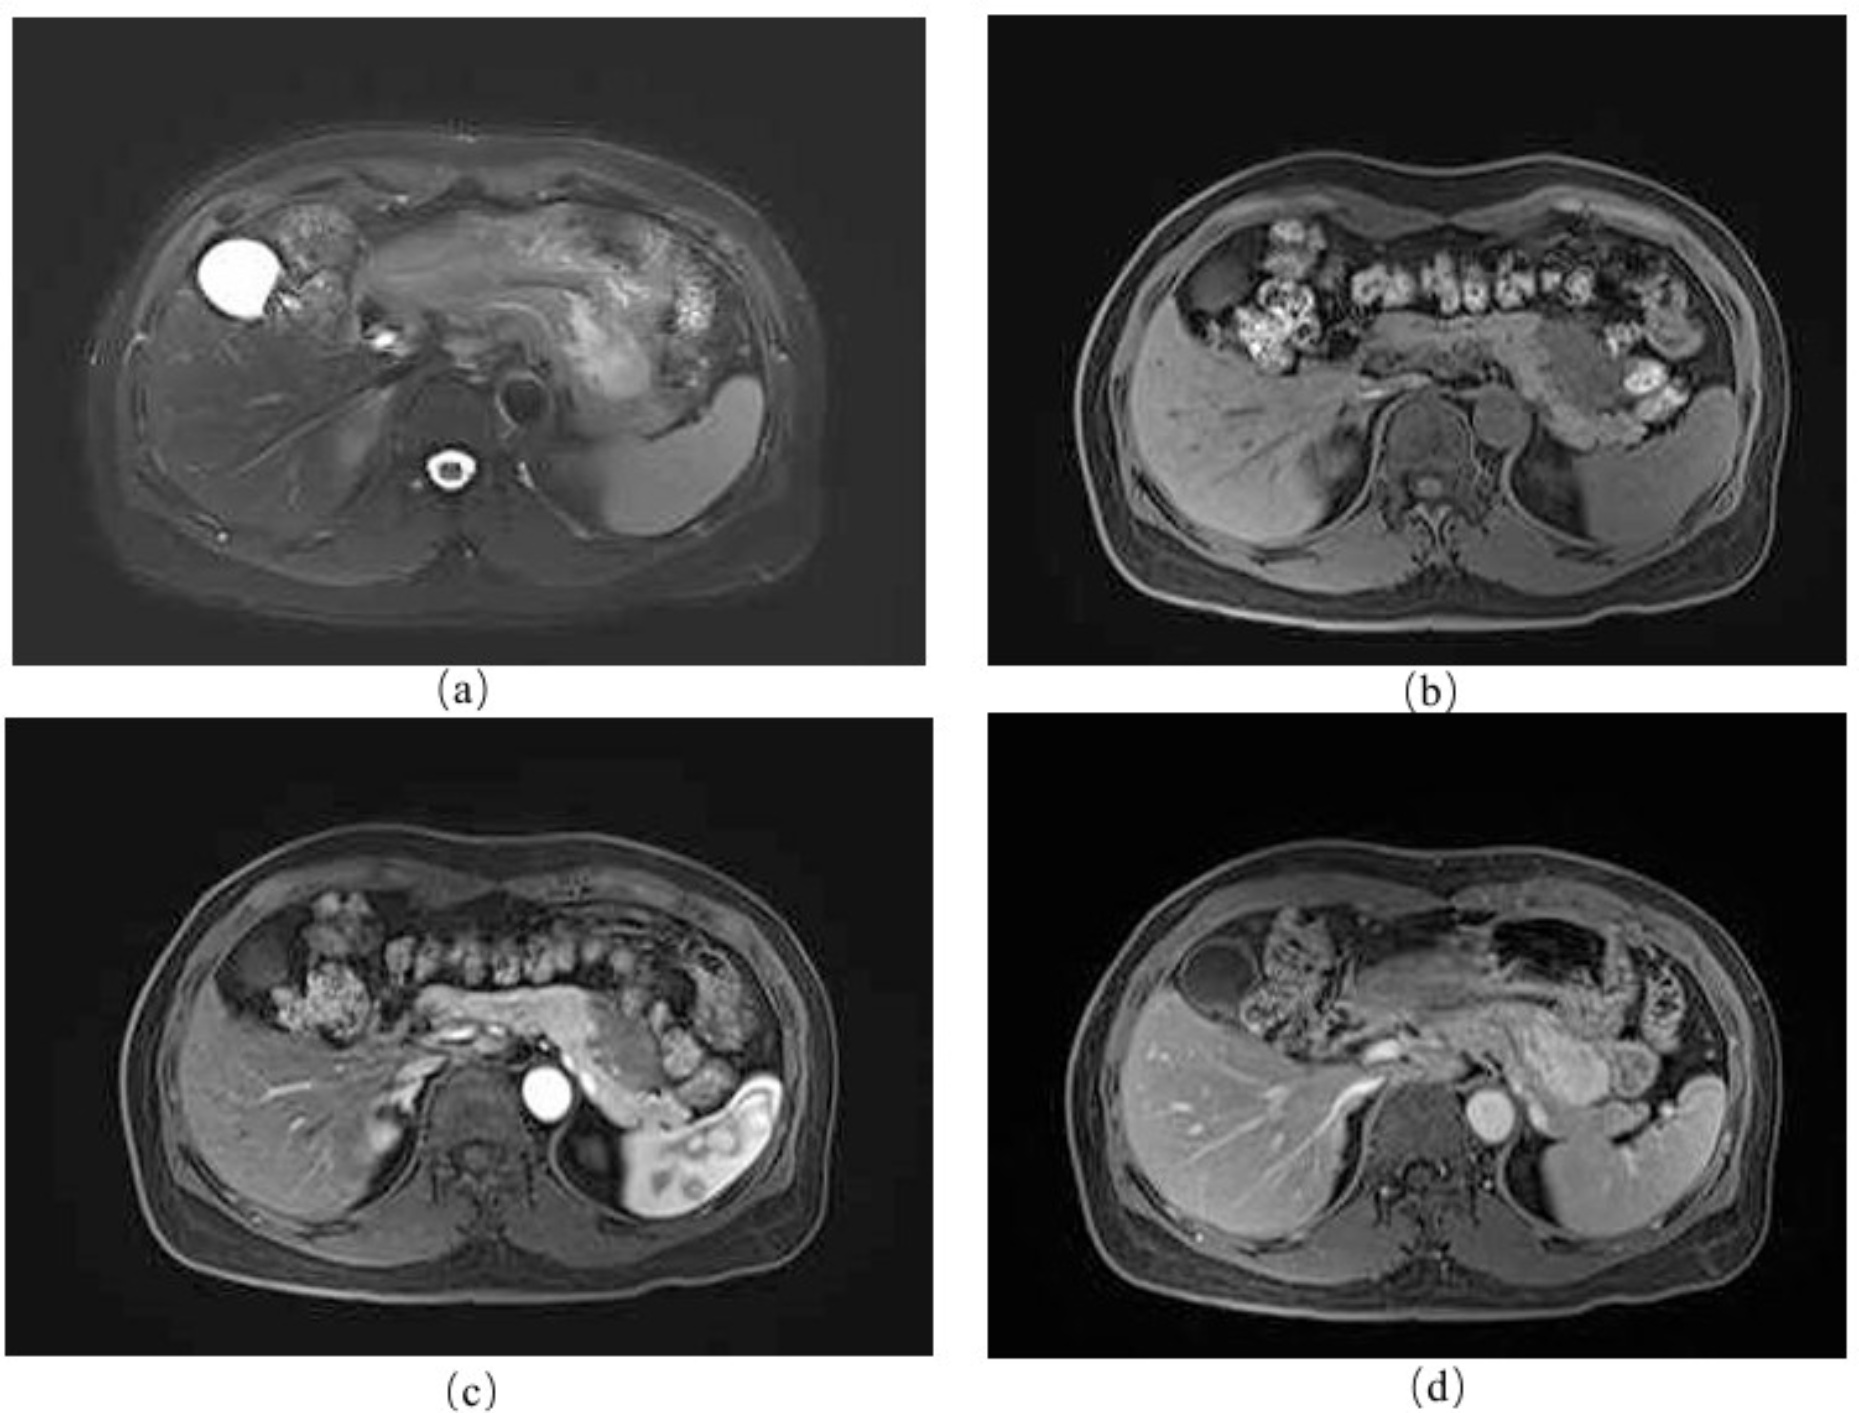

患者女性,49岁,因“腹痛20天”入院,腹痛位于剑突下,阵发性,进食后出现,持续数小时后缓解。患者既往患有高血压、高血脂及颈动脉硬化,药物治疗。起初患者于消化内科接受解痉、护胃、抗感染治疗,未见好转。实验室检查无殊,腹部B超见41*18 mm低回声区,边界尚清,可见点状血流信号。完善检查,CT平扫 + 增强扫描提示胰腺体尾部可见不规则软组织密度团块影,大小约47*35 mm,增强呈渐进式中度强化,内见坏死,与周围脏器边界欠清(如图1)。MRI平扫 + 增强提示肿块位于胰腺体尾部,与胃小弯毗邻,T1WI呈低信号,压脂T2WI呈混杂稍高信号,实性部分弥散受限,动脉期病灶呈不均匀低强化,门脉期实性部分进一步强化,与胰腺及胃分界欠清(如图2)。首先考虑消化系统恶性肿瘤。

注:(a) T1WI:瘤体呈低信号;(b) T2WI:瘤体呈混杂高信号,弥散受限;(c) 动脉期:瘤体呈渐进式不均匀强化;(d) 门脉期:瘤体与正常胰腺强化一致。

Figure 2. Preoperative abdominal enhanced MRI examination

2. 患者术前腹部增强MRI检查